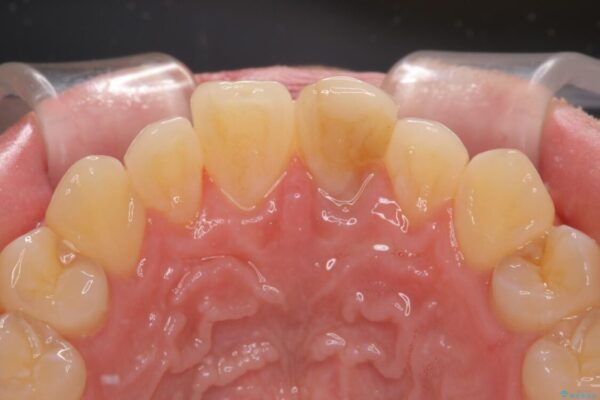

神経を取り除いたことで変色した前歯を気にして来院された患者様です。

治療前

• 変色した前歯をオールセラミッククラウンに 治療前画像